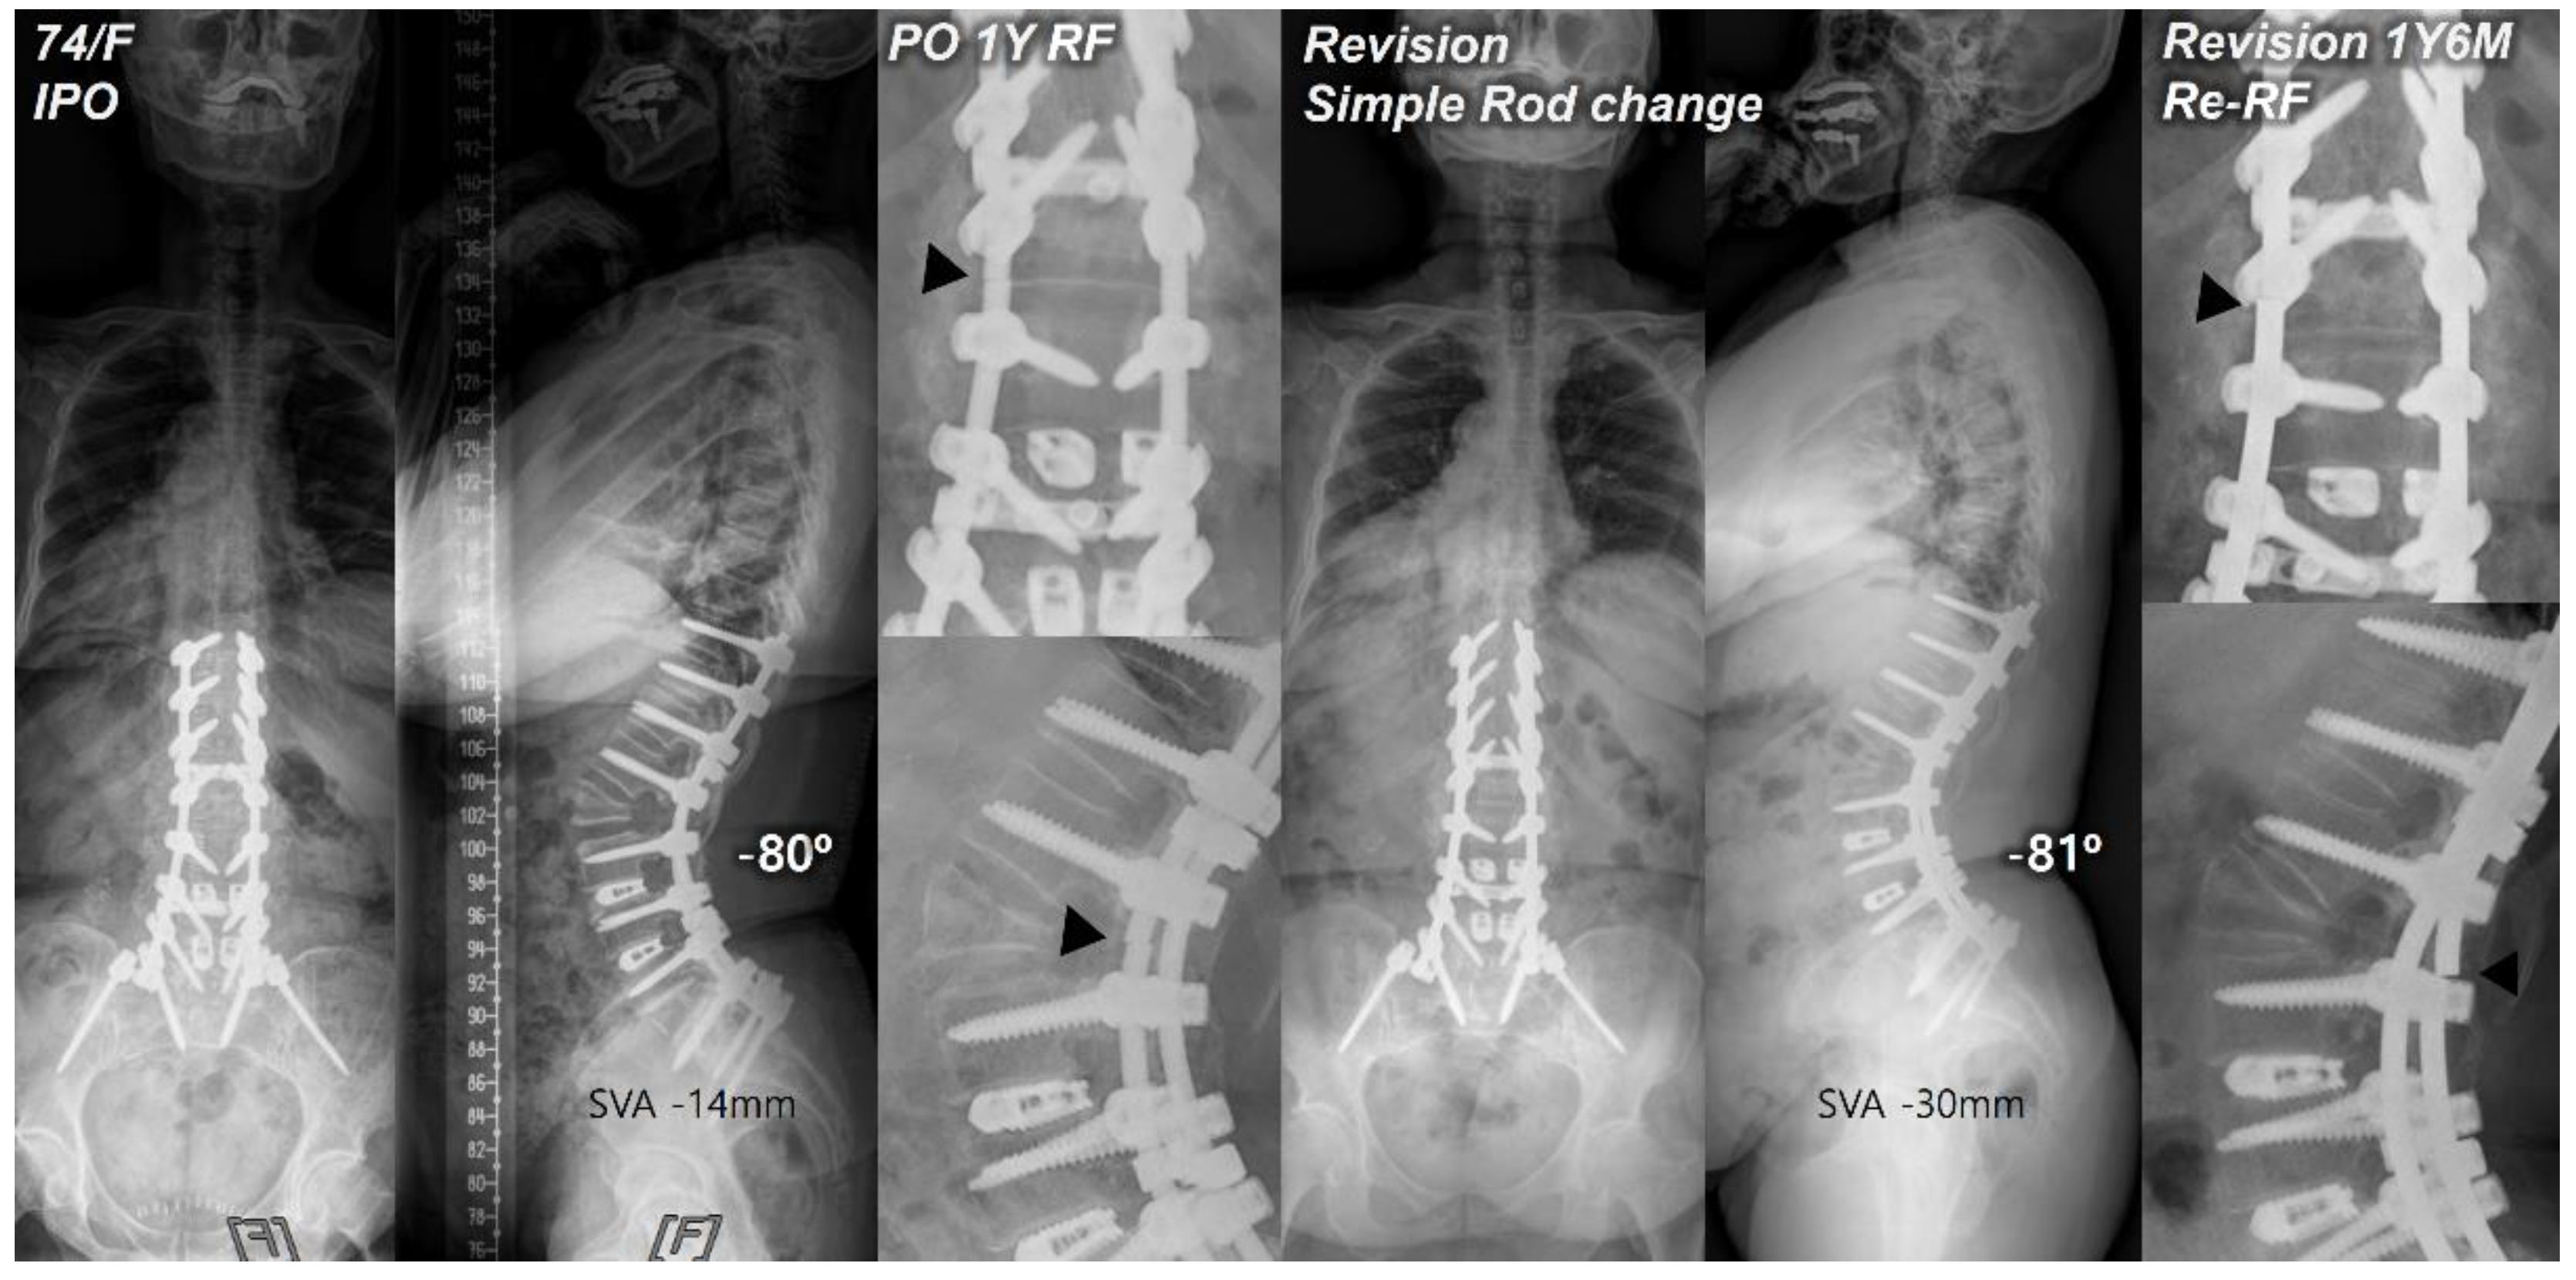

Figure 1. Postoperative standing radiographs of a 74-year-old female patient after T10-S1 posterior instrumentation with PSO on L2, PLIF on L3-5, and ALIF on L5-S1 with an optimal sagittal balance (SVA, -14 mm; TK, 28°; LL, -80°; PI, 54°; PT, 4°; SS, 50°). At 1 year after primary deformity correction, RF (left rod) occurred at L2. At 1 year and 6 months following revision surgery with simple bilateral rod replacement, re-RF occurred at L2-3. Black triangles indicate the site of RF.

Our study findings revealed the incidence of re-RF following revision surgery due to RF to be 13%. Of the three revision methods, simple bilateral rod replacement (SR group) showed the highest incidence of re-RF. We believe that the hyper-acutely contoured posterior rods paralleling a relatively large angular correction in PSO, could have progressively intensified the stress concentration and lowered the fatigue strength of each rod [17,18,19,20,21], which consequently may have led to rod-breakage. Furthermore, the fact that every re-RF in the SR group occurred consistently at the same PSO site (Figure 1), not only suggests that simple bilateral rod replacement alone has a high risk of re-RF, but also proves that additional support around the PSO site is ultimately required to prevent RF and maintain sagittal balance in PSO.